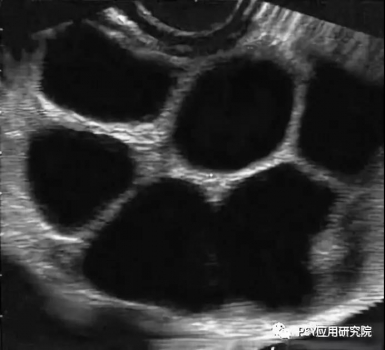

進(jìn)入高溫季節(jié)以后,很多豬場(chǎng)的配懷率開始出現(xiàn)下降,返情率表現(xiàn)上升,屢配不孕的現(xiàn)象有所抬頭,這種情況不僅會(huì)導(dǎo)致母豬非正常生產(chǎn)天數(shù)的增加,而且也會(huì)降低豬場(chǎng)PSY,那么導(dǎo)致母豬發(fā)生高返情率的原因包括哪些呢? 圖1母豬受孕后出現(xiàn)的不同返情時(shí)間 原因之一:發(fā)情鑒定失誤 對(duì)母豬進(jìn)行發(fā)情鑒定是人工授精的前提,一旦發(fā)情鑒定失誤,對(duì)未發(fā)情的母豬進(jìn)行授精,那么母豬將在配種后的19天之內(nèi)出現(xiàn)返情。 發(fā)情鑒定失敗的原因有二: ➤一方面是由于配種員的經(jīng)驗(yàn)不夠, ➤另一方面也與母豬的品種與個(gè)體發(fā)情表現(xiàn)不明顯有關(guān)。 建議:在每天上午8點(diǎn)和下午5點(diǎn),每天兩次使用公豬對(duì)斷奶母豬和適齡后備母豬進(jìn)行輔助發(fā)情鑒定,加強(qiáng)對(duì)母豬發(fā)情表現(xiàn)的辨認(rèn)度,提高發(fā)情鑒定成功率。 圖2 靜立反應(yīng) 原因之二:霉菌毒素污染 在所有霉菌毒素中,玉米赤霉烯酮是對(duì)母豬生殖系統(tǒng)危害最為嚴(yán)重的霉菌毒素,它具有類雌激素作用,可促使母豬出現(xiàn)假發(fā)情,但母豬并未排卵,因此配種后又會(huì)在很短時(shí)間(多發(fā)生19天以內(nèi))出現(xiàn)返情。 建議:豬場(chǎng)加強(qiáng)對(duì)飼料原料的控制,尤其是在夏季母豬飼料中應(yīng)降低米糠或麩皮的添加比例,控制貯存時(shí)間,可使用膳食纖維等替代品、加強(qiáng)對(duì)料槽、料線的清理以及添加霉菌毒素吸附劑的方法來減輕危害。 原因之三:卵巢囊腫 母豬發(fā)生卵巢囊腫以后,由于分泌過多的卵泡素,母豬性欲旺盛,經(jīng)常趴跨其他母豬,但屢配不孕,其原因在于:由于母豬排卵遲滯,精子在母豬排卵之前已喪失受精能力,導(dǎo)致母豬受孕失敗,這類返情多發(fā)生在配種后的19天以內(nèi)。 建議:一旦發(fā)現(xiàn)母豬持續(xù)發(fā)情且屢配不孕,給母豬肌注黃體酮、促黃體素釋放激素或人絨毛膜促性激素,每日1次,連用2-4次。 圖3 卵巢囊腫B超圖 原因之四:精液品質(zhì)下降 使用不合格的公豬精液進(jìn)行輸精,母豬將在19-23天左右出現(xiàn)返情。 這種問題在夏季、秋季高發(fā),研究發(fā)現(xiàn)公豬對(duì)熱應(yīng)激高度敏感,在環(huán)境溫度超過30℃以后,無論是精子活力還是精子密度,均會(huì)出現(xiàn)明顯下降,造成母豬受孕率大幅下降,而且公豬精液品質(zhì)下降后,其恢復(fù)正常所需時(shí)間在2個(gè)月左右。 因此建議:夏季必須采取有效措施對(duì)公豬進(jìn)行降溫,避免熱應(yīng)激對(duì)公豬的不利影響,同時(shí)在飼料中添加抗應(yīng)激產(chǎn)品,并控制公豬的使用強(qiáng)度,避免過度使用。 原因之五:輸精時(shí)間不當(dāng) 一般而言:母豬在發(fā)情后的24-36h進(jìn)行排卵,排卵持續(xù)時(shí)間為10-15h,卵子保持受精能力的時(shí)間為8-10h,精子達(dá)到受精部位所需的時(shí)間為2-3h,因此最佳的輸精時(shí)間為母豬排卵前的2-3h,由于輸精時(shí)間不當(dāng)而導(dǎo)致的返情多發(fā)生在配種后的19-23天。 建議:在無試情公豬條件下,可采用下表進(jìn)行人工授精。 原因之六:子宮復(fù)舊不全 研究發(fā)現(xiàn):母豬在分娩過程中,無論是順產(chǎn)還是助產(chǎn),子宮都會(huì)有不同程度的損傷,子宮復(fù)舊不全將導(dǎo)致母豬出現(xiàn)返情,一般發(fā)生在配種后的19-23天。 為確保子宮復(fù)舊完全,需要做到以下三點(diǎn):盡量避免掏產(chǎn),加強(qiáng)母豬產(chǎn)后護(hù)宮,在母豬產(chǎn)后使用宮炎凈,促進(jìn)子宮黏膜修復(fù)和生長;給予足夠的復(fù)舊時(shí)間,確保泌乳時(shí)間不低于19天;配懷舍溫度控制在24℃左右,給母豬創(chuàng)造良好條件。 圖4 子宮復(fù)舊良好的母豬 原因之七:飼養(yǎng)管理不當(dāng) 母豬在配種后的30天之內(nèi)是胚胎死亡的高峰期,造成胚胎死亡的原因包括:各種應(yīng)激(熱、冷、噪音、驚嚇、免疫、驅(qū)蟲)、飼喂過多或過高能量飼料,研究發(fā)現(xiàn):母豬建立穩(wěn)定的妊娠狀態(tài)至少需要5枚胚胎,低于這個(gè)數(shù)量將導(dǎo)致母豬在懷孕后的19-23天出現(xiàn)返情。 建議:在配種后的30天內(nèi),對(duì)母豬進(jìn)行嚴(yán)格限飼,并添加青綠飼料或膳食纖維,采用“六不一優(yōu)”技術(shù),在配種的30天母豬飼喂量控制1.8-2.2kg左右,減少各種應(yīng)激,保持配懷舍安靜和涼爽,并在飼料中添加生殖營養(yǎng)(如:仔多多),可促進(jìn)母豬分泌子宮乳和胚胎著床,減少胚胎死亡。 圖 5 “六不一優(yōu)”技術(shù) 原因之八:疾病因素 目前豬場(chǎng)導(dǎo)致母豬出現(xiàn)返情的主要疾病包括:藍(lán)耳病、偽狂犬、豬瘟、細(xì)小病毒、乙腦等。尤其是夏季高溫季節(jié),在懷孕中期出現(xiàn)的流產(chǎn),乙腦、細(xì)小病毒是需要重點(diǎn)關(guān)注的致病原。 建議:豬場(chǎng)每年需檢測(cè)藍(lán)耳病、偽狂犬、豬瘟等主要疾病抗體水平;每年4月底之前對(duì)所有種豬普免乙腦,對(duì)第一胎、第二胎母豬普免細(xì)小病毒疫苗。 小結(jié): 豬場(chǎng)應(yīng)在母豬配種后的21天,使用B超進(jìn)行妊娠鑒定,母豬發(fā)生返情以后,需要記錄返情發(fā)生時(shí)間、返情比例,根據(jù)其返情規(guī)律確定其可能的原因,再采取對(duì)應(yīng)的措施,方能將返情率控制在8%以下比較合理的水平。 原創(chuàng): 劉輝旺 來源:PSY應(yīng)用研究院 |